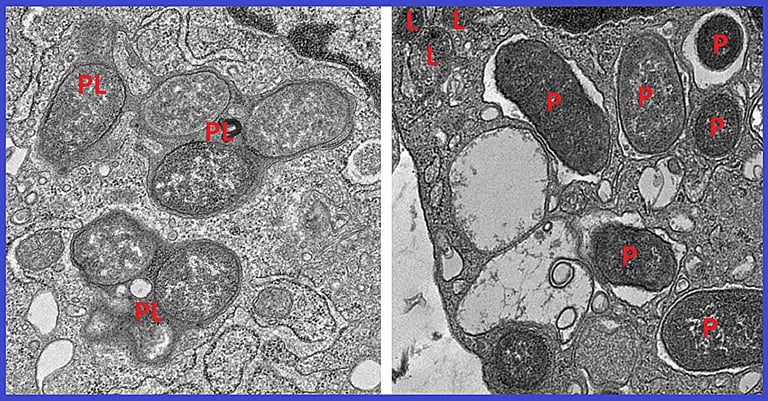

Within both diseased and healthy colon tissue, girdin emerges as a key protein in non-inflammatory, tissue-healing macrophages, as revealed by the gene signature analysis.

In non-inflammatory macrophages, a region of NOD2 binds girdin to suppress excessive inflammation, clear microbes, and promote tissue repair, while most common Crohn’s mutations delete this girdin-binding region, causing imbalance.

Under healthy conditions, NOD2 interacts with girdin to maintain gut immune balance through inflammation suppression and tissue repair; mutations often remove the girdin-binding region, tipping the balance toward disease.